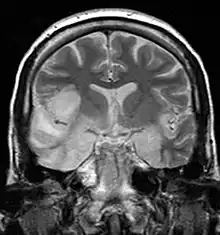

| MRI scan image shows high signal in the temporal lobes and right inferior frontal gyrus in someone with herpes simplex encephalitis. | |